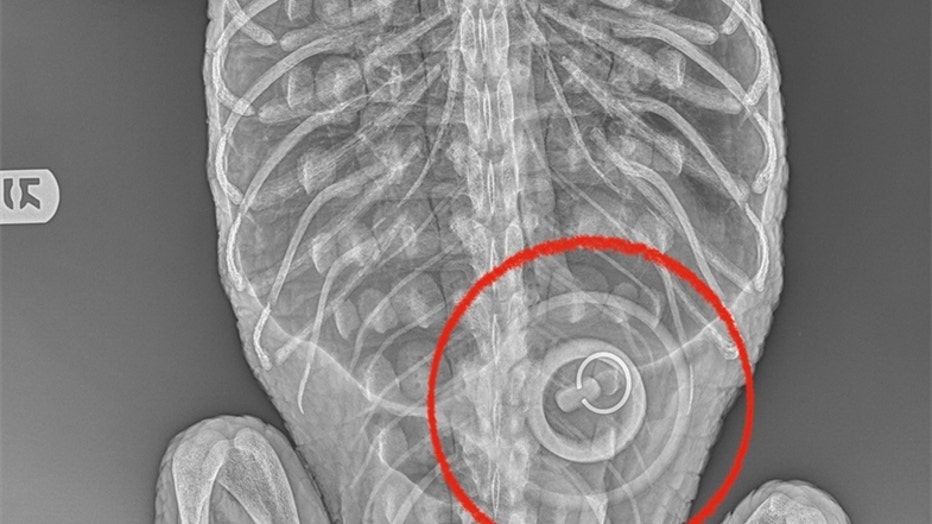

The female alligator was found on Feb. 19 in Prospect Park Lake in 37-degree Fahrenheit temperature water. The animal was taken to the Bronx Zoo, which discovered that she had ingested a 4-inch wide bathtub stopper.

The alligator found in Brooklyn's Prospect Park Lake had swallowed a bathtub stopper. (Credit: Bronx Zoo)